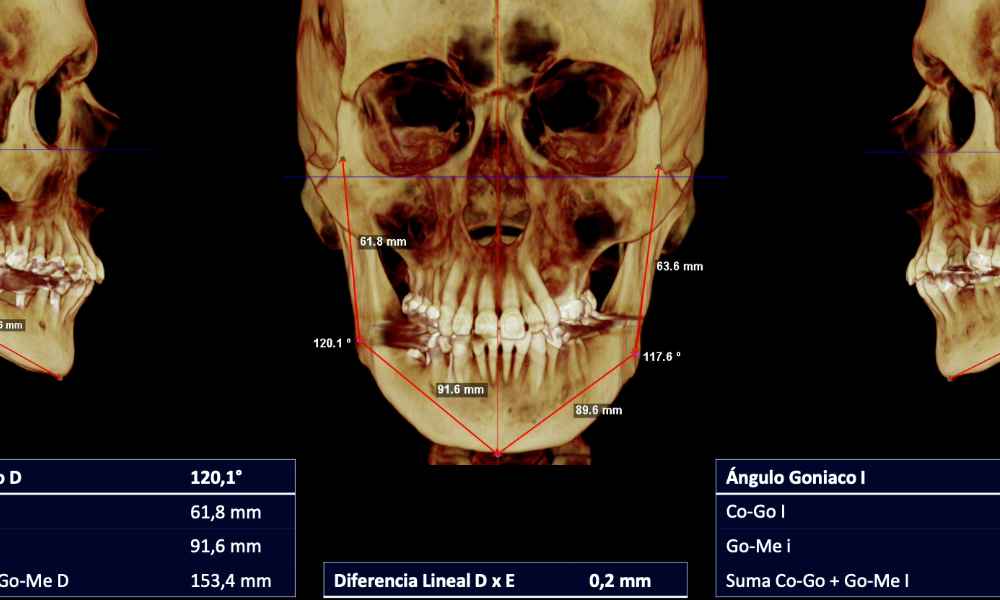

DIAGNÓSTICO 3D

Actualmente contamos la Tomografía Axial Computarizada (TAC) que nos ofrece muchísima más información y la posibilidad de reconstrucciones 3D